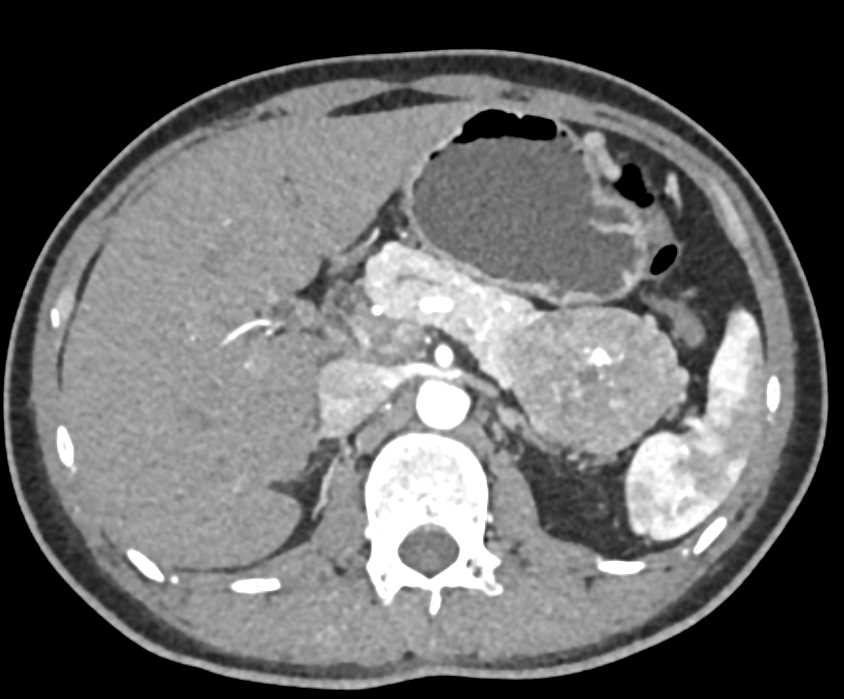

PNET Tail of the Pancreas